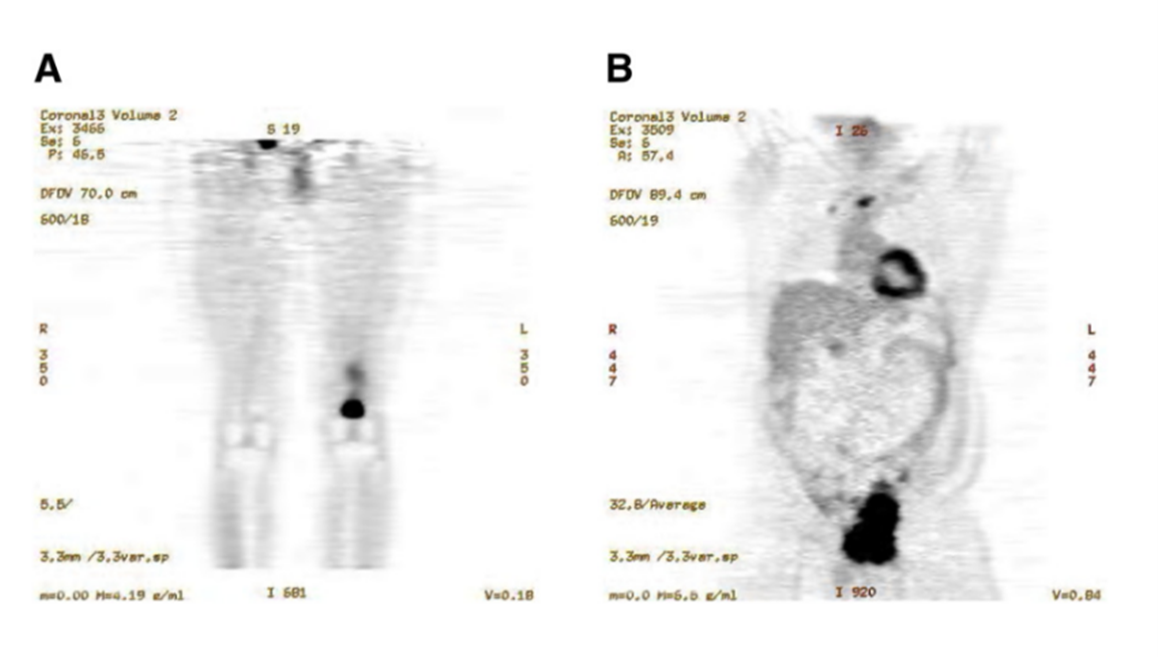

图2 原发性肉瘤肿瘤患者的18F-FDG PET 图像。 (A) 左侧股骨骨平滑肌瘤患者的冠状面图像。 (B) 右侧骨盆血管肉瘤患者的冠状面图像。

影像学评估在软组织肉瘤的初筛、分期以及手术可切除性判断中起到关键作用。磁共振成像 (MRI) 因其在显示肿瘤边界、内部结构、与邻近组织关系及血供情况方面的高分辨率,被认为是评估软组织肿瘤的首选影像手段,尤其适用于四肢、盆腔或躯干深部病灶。计算机断层扫描 (CT) 在肺部远处转移的评估中具有重要地位,是确诊期及随访期间不可或缺的检查方法。正电子发射断层扫描 (PET-CT) 则对代谢活跃或疑似远处转移的肉瘤亚型具有补充价值,不仅有助于原发灶和转移灶的识别,也在治疗应答监测和复发评估中发挥作用[2]。不同成像方式间的协同应用可提高诊断的全面性和准确性,在治疗路径选择中也具有参考价值。